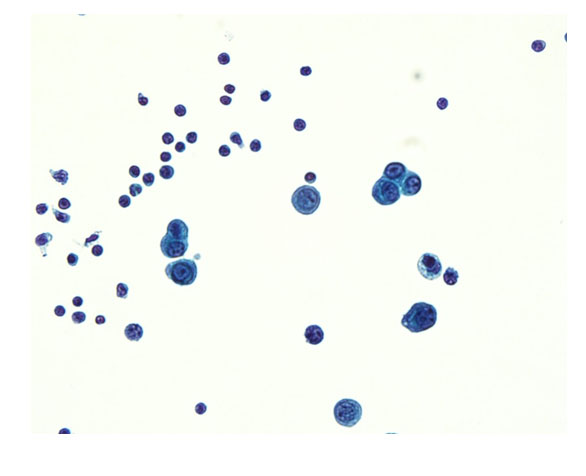

The patient was admitted to the hepatology inpatient service with consults from rheumatology, infectious disease, hematology, nephrology, pulmonology, and interventional radiology for a multidisciplinary approach to management. He underwent paracentesis followed by thoracentesis and an ultrasound guided peritoneal nodule biopsy. Turbid white chylous fluid (1200 mL) was removed from the left chest. The initial clinical impression from pulmonary was that the bilateral chylous effusion was likely secondary to superior vena cava syndrome and left brachiocephalic obstruction caused by lymphadenopathy. He was commenced on a low cholesterol diet and nutrition was consulted. Laboratory results from the first peritoneal tap showed atypical mesothelial cells indeterminate for malignancy (Figure 2). Subsequent thoracentesis (Figure 3) and paracentesis (Figure 4) specimens had higher cellular yield and revealed highly atypical mesothelial cells with high nuclear to cytoplasmic ratios and prominent nucleoli suggestive of malignant mesothelioma. Tumor cells were immunoreactive with Calretinin immunohistochemistry stain (Figure 5) which supported mesothelial origin rather than an epithelial origin (carcinoma). The diagnosis was further confirmed by an ultrasound guided peritoneal nodule biopsy which showed a consolidation of epithelioid tumor cells consistent with malignant mesothelioma, epithelioid type (Figure 6). Immunohistochemical staining of the omental biopsy for Ki 67 staining showed a high proliferative index > 10% (Figure 7). The tumor also contained foci of inflammatory cells including many plasma cells. These inflammatory cells could be reactive to the tumor or related to an underlying autoimmune or inflammatory process.

Figure 3: Pleural fluid. Malignant mesothelioma, cytospin, Diff Quik stain, high power.

Share Image: